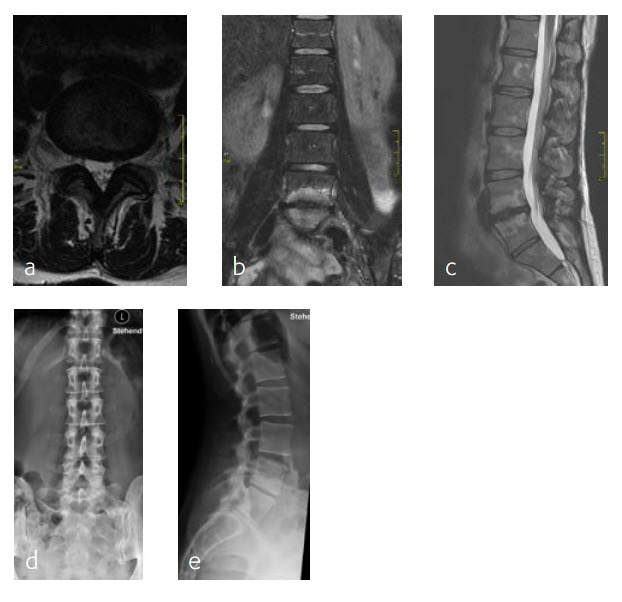

Anterior lumbar interbody fusion surgery was undertaken in July 2016 using the Synfix Evolution with InductOs (6 mg) (Fig 7). Intraoperative: routine operation, no complications. Postoperative: uneventful postoperative course.